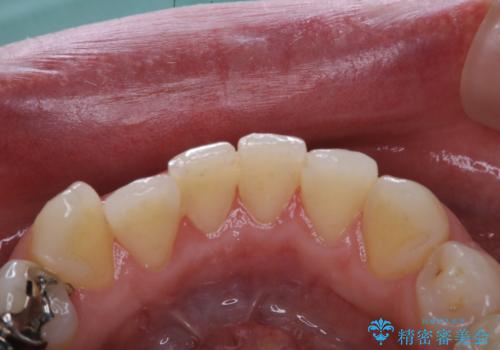

歯科衛生士によるPMTCでお口のケア

- 歯医者に来院することが久しぶりで、まずはクリーニングを希望とのことでした。コースや内容は、一番状態に合ったものでとのことだったため、PMTC60分コースを行いました。

汚れを除去することにより、症状の早期発見につながります。

定期的に歯科医院に来院し、PMTCを行うことが大切です。